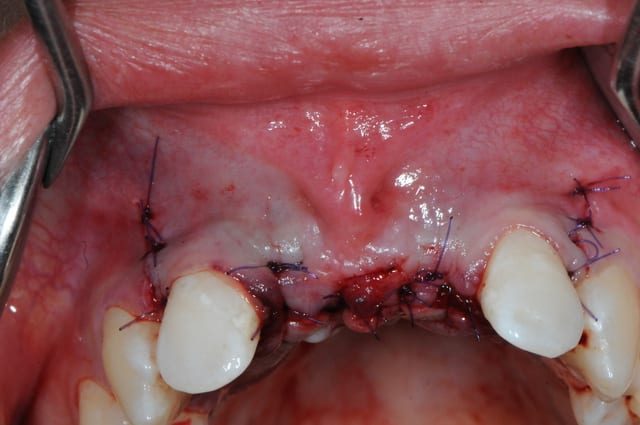

juste pour le plaisir des yeux...

j'étais hier à Strasbourg dans une formation avec Fouad Khoury.

oui biobank et granules de biobank par dessus.

La chir et les photos sont magnifiques, mais je partage certaines réflexions de Jeff.

C'est un très joli travail tout d'abord, mais ton frein ne risque-t-il pas de gêner, si oui, tu comptes faire la chir mucco après ?

PS : l'angle de la photo est peut-être trompeur...